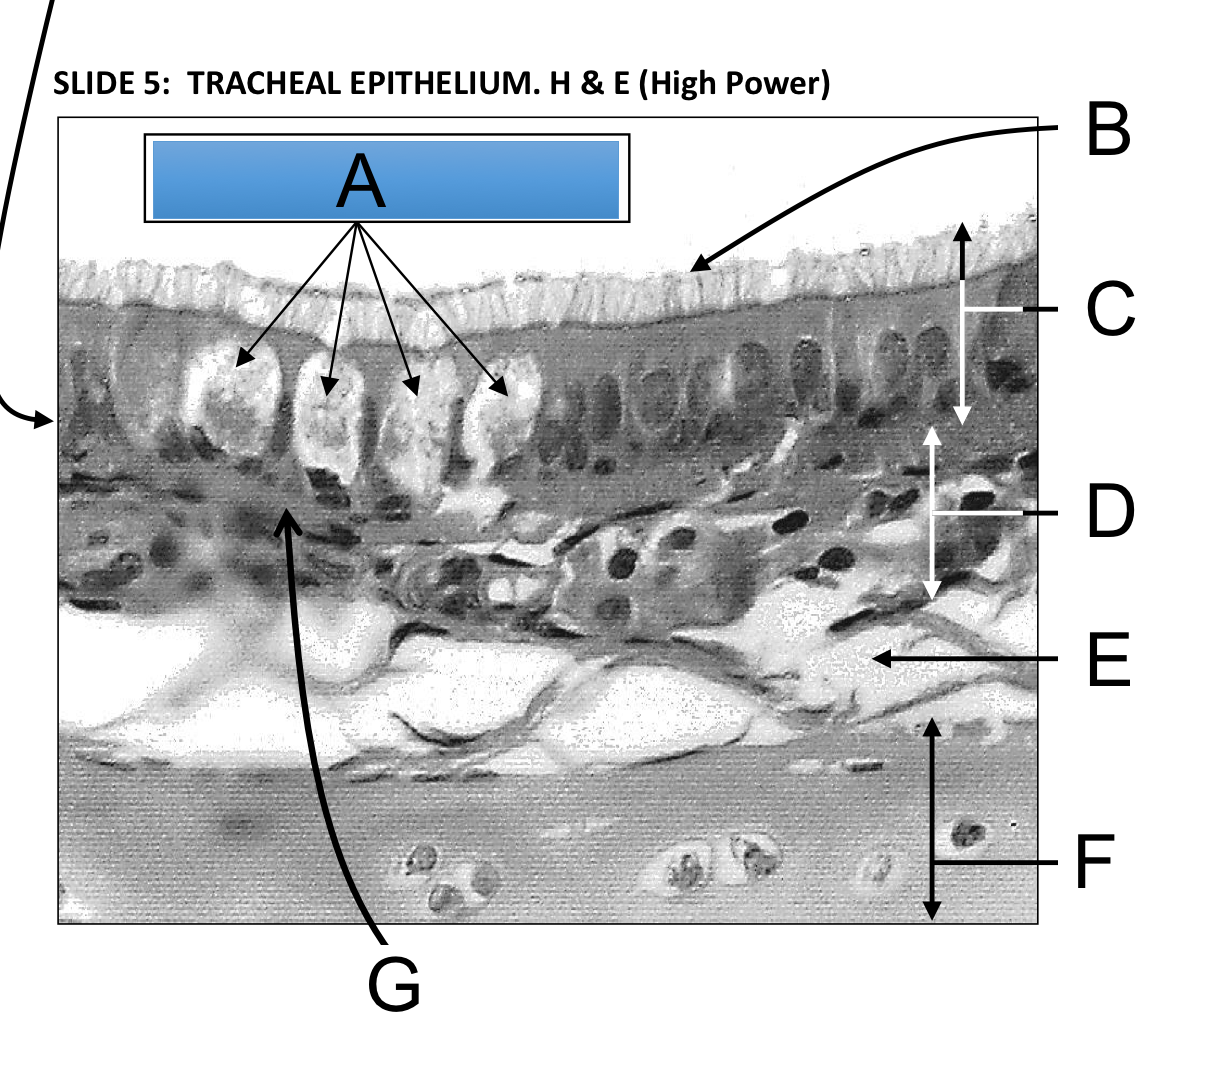

A - Mucus secreting goblet cells

B - Cilia line the upper respiratory tract

C - Pseudostratified ciliated columnar epithelim lines the tracheal lumen

D - Submucosa containing seromucous glands (depth varies depending on location)

E - An artefactual split in the perichondrium

F - Hyaline cartilage containing chondrocytes

G - The basement membrane of respiratory epithelium (can only really be seen on tracheal slide with H & E stain)